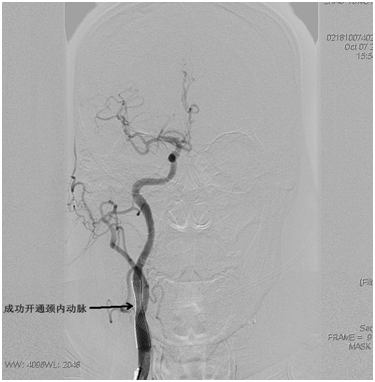

韩金涛副主任医师凭借丰富的临床经验,判断本次急性脑梗塞的根源在于右侧颈内动脉起始段急性闭塞(图1)。在从家中赶来支援的贾子昌主治医师和隋玉洁主管护师的熟练配合下,沉着而迅速进行了闭塞的右侧颈内动脉急诊成形术。历时不到1小时,患者的右侧颈内动脉得以恢复通畅血流(图2)。术后即刻,尚躺在手术床上的患者神志即恢复清醒,而且左侧肢体肌力恢复至较满意水平(图3-4)。

图2